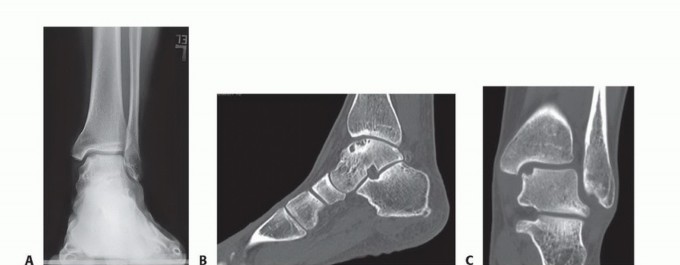

DEFINITION The term osteochondral lesion of the talus (OLT) refers to any pathology of the talar articular ca…

DEFINITION Osteochondral lesions of the talus (OLT) are common conditions that can involve both the cartilage…